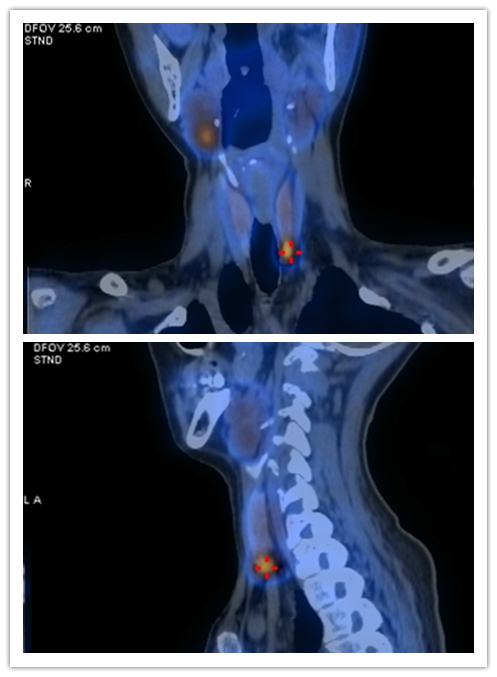

接诊的内分泌二病区主任赵新兰仔细询问病史、体查后发现,患者不是糖尿病,而有可能是一种较为少见的甲状旁腺亢进症(简称甲旁亢)。经检查,最终确定彭女士反复发作的泌尿系结石、逐渐加重的疲倦感等症状,都是由于体内的甲状旁腺瘤分泌过多的甲状旁腺激素所导致。目前经一系列治疗,5月20日,彭女士血钙恢复正常,症状好转出院。